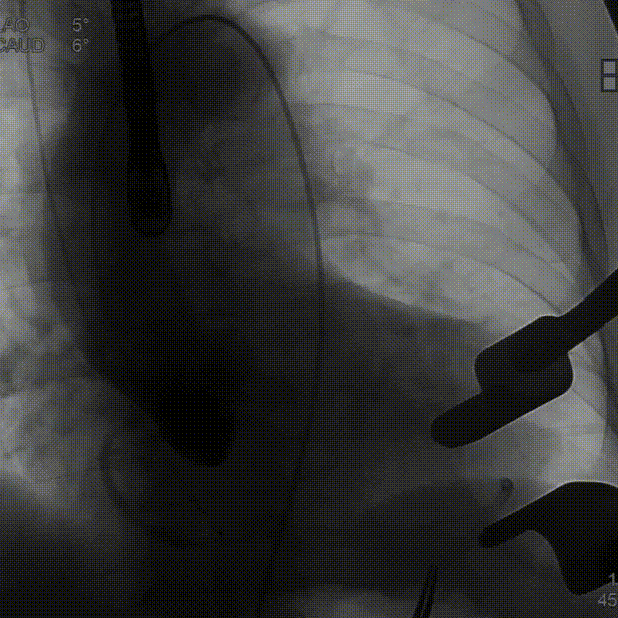

定位件入窦后造影:

降瓣至窦部:

完成瓣膜释放: